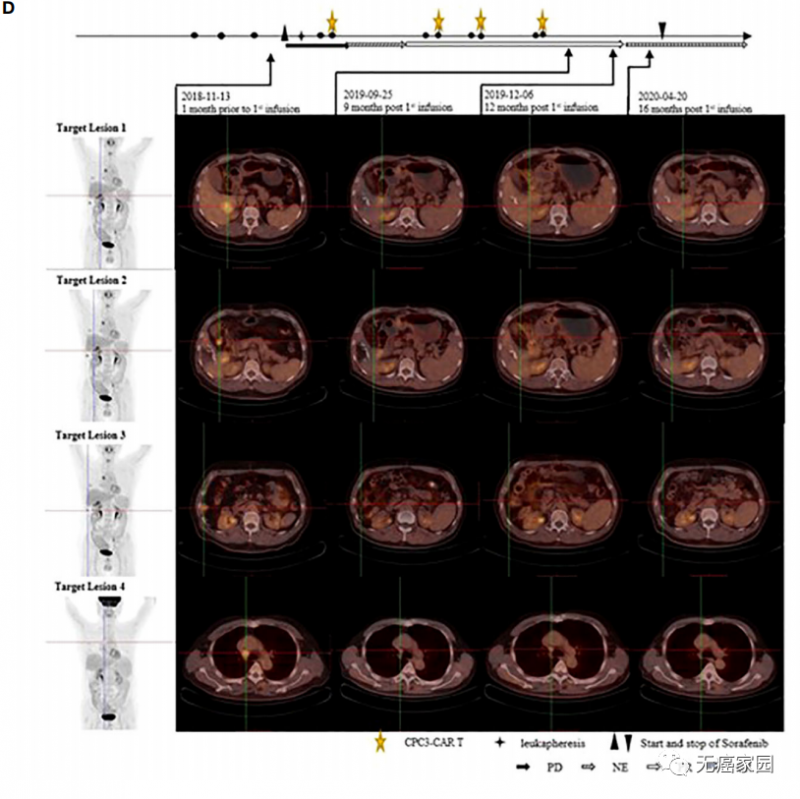

靶病变PET-CT图像

(患者在基线时接受PET-CT检查,首次输注后6、9、12、16个月。1号、2号和3号靶病变在第12个月消失,而4号靶病变病变不活跃,在抗肿瘤治疗后被认为是非特异性摄取)